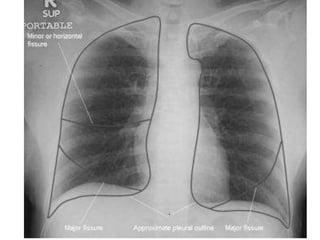

CXR